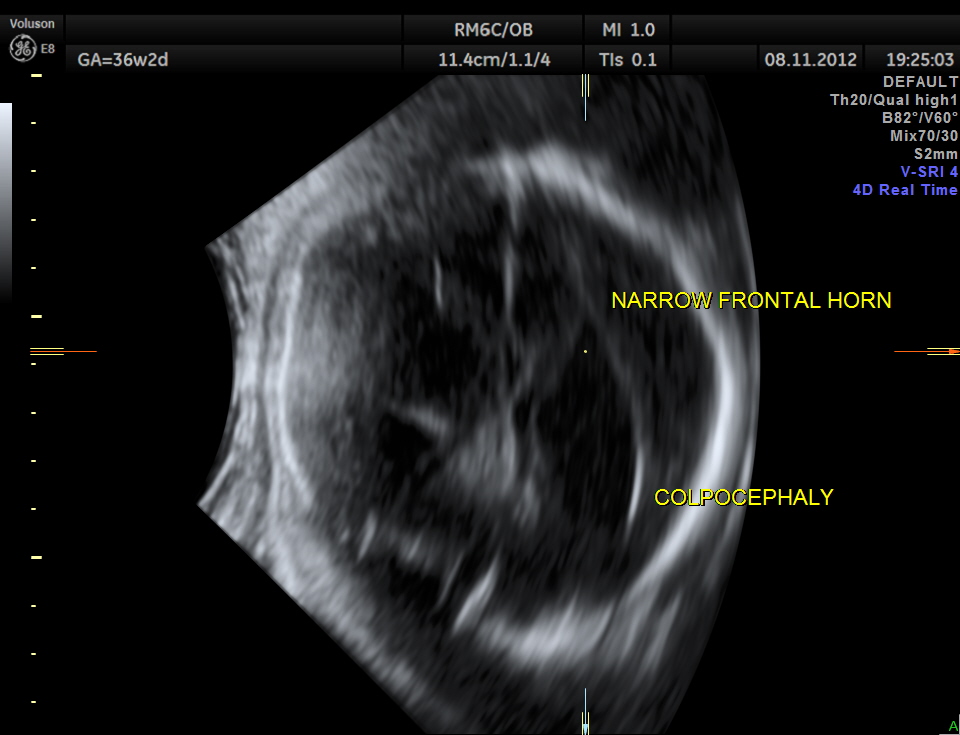

prominent ventriculomegaly of posterior horns of both lateral ventricles – colpocephaly

demonstration of both medial and lateral ventricular walls at a level where the single periventricular line is normally demonstrated

- disproportionate enlargement of the occipital horn,

- demonstration of both medial and lateral ventricular walls at a level where the single periventricular line is normally demonstrated, and

- a more parallel course of both ventricular walls than normal.

They suggested that demonstration of these findings on axial views should stimulate additional coronal and sagittal views for evaluation of agenesis of the corpus callosum.